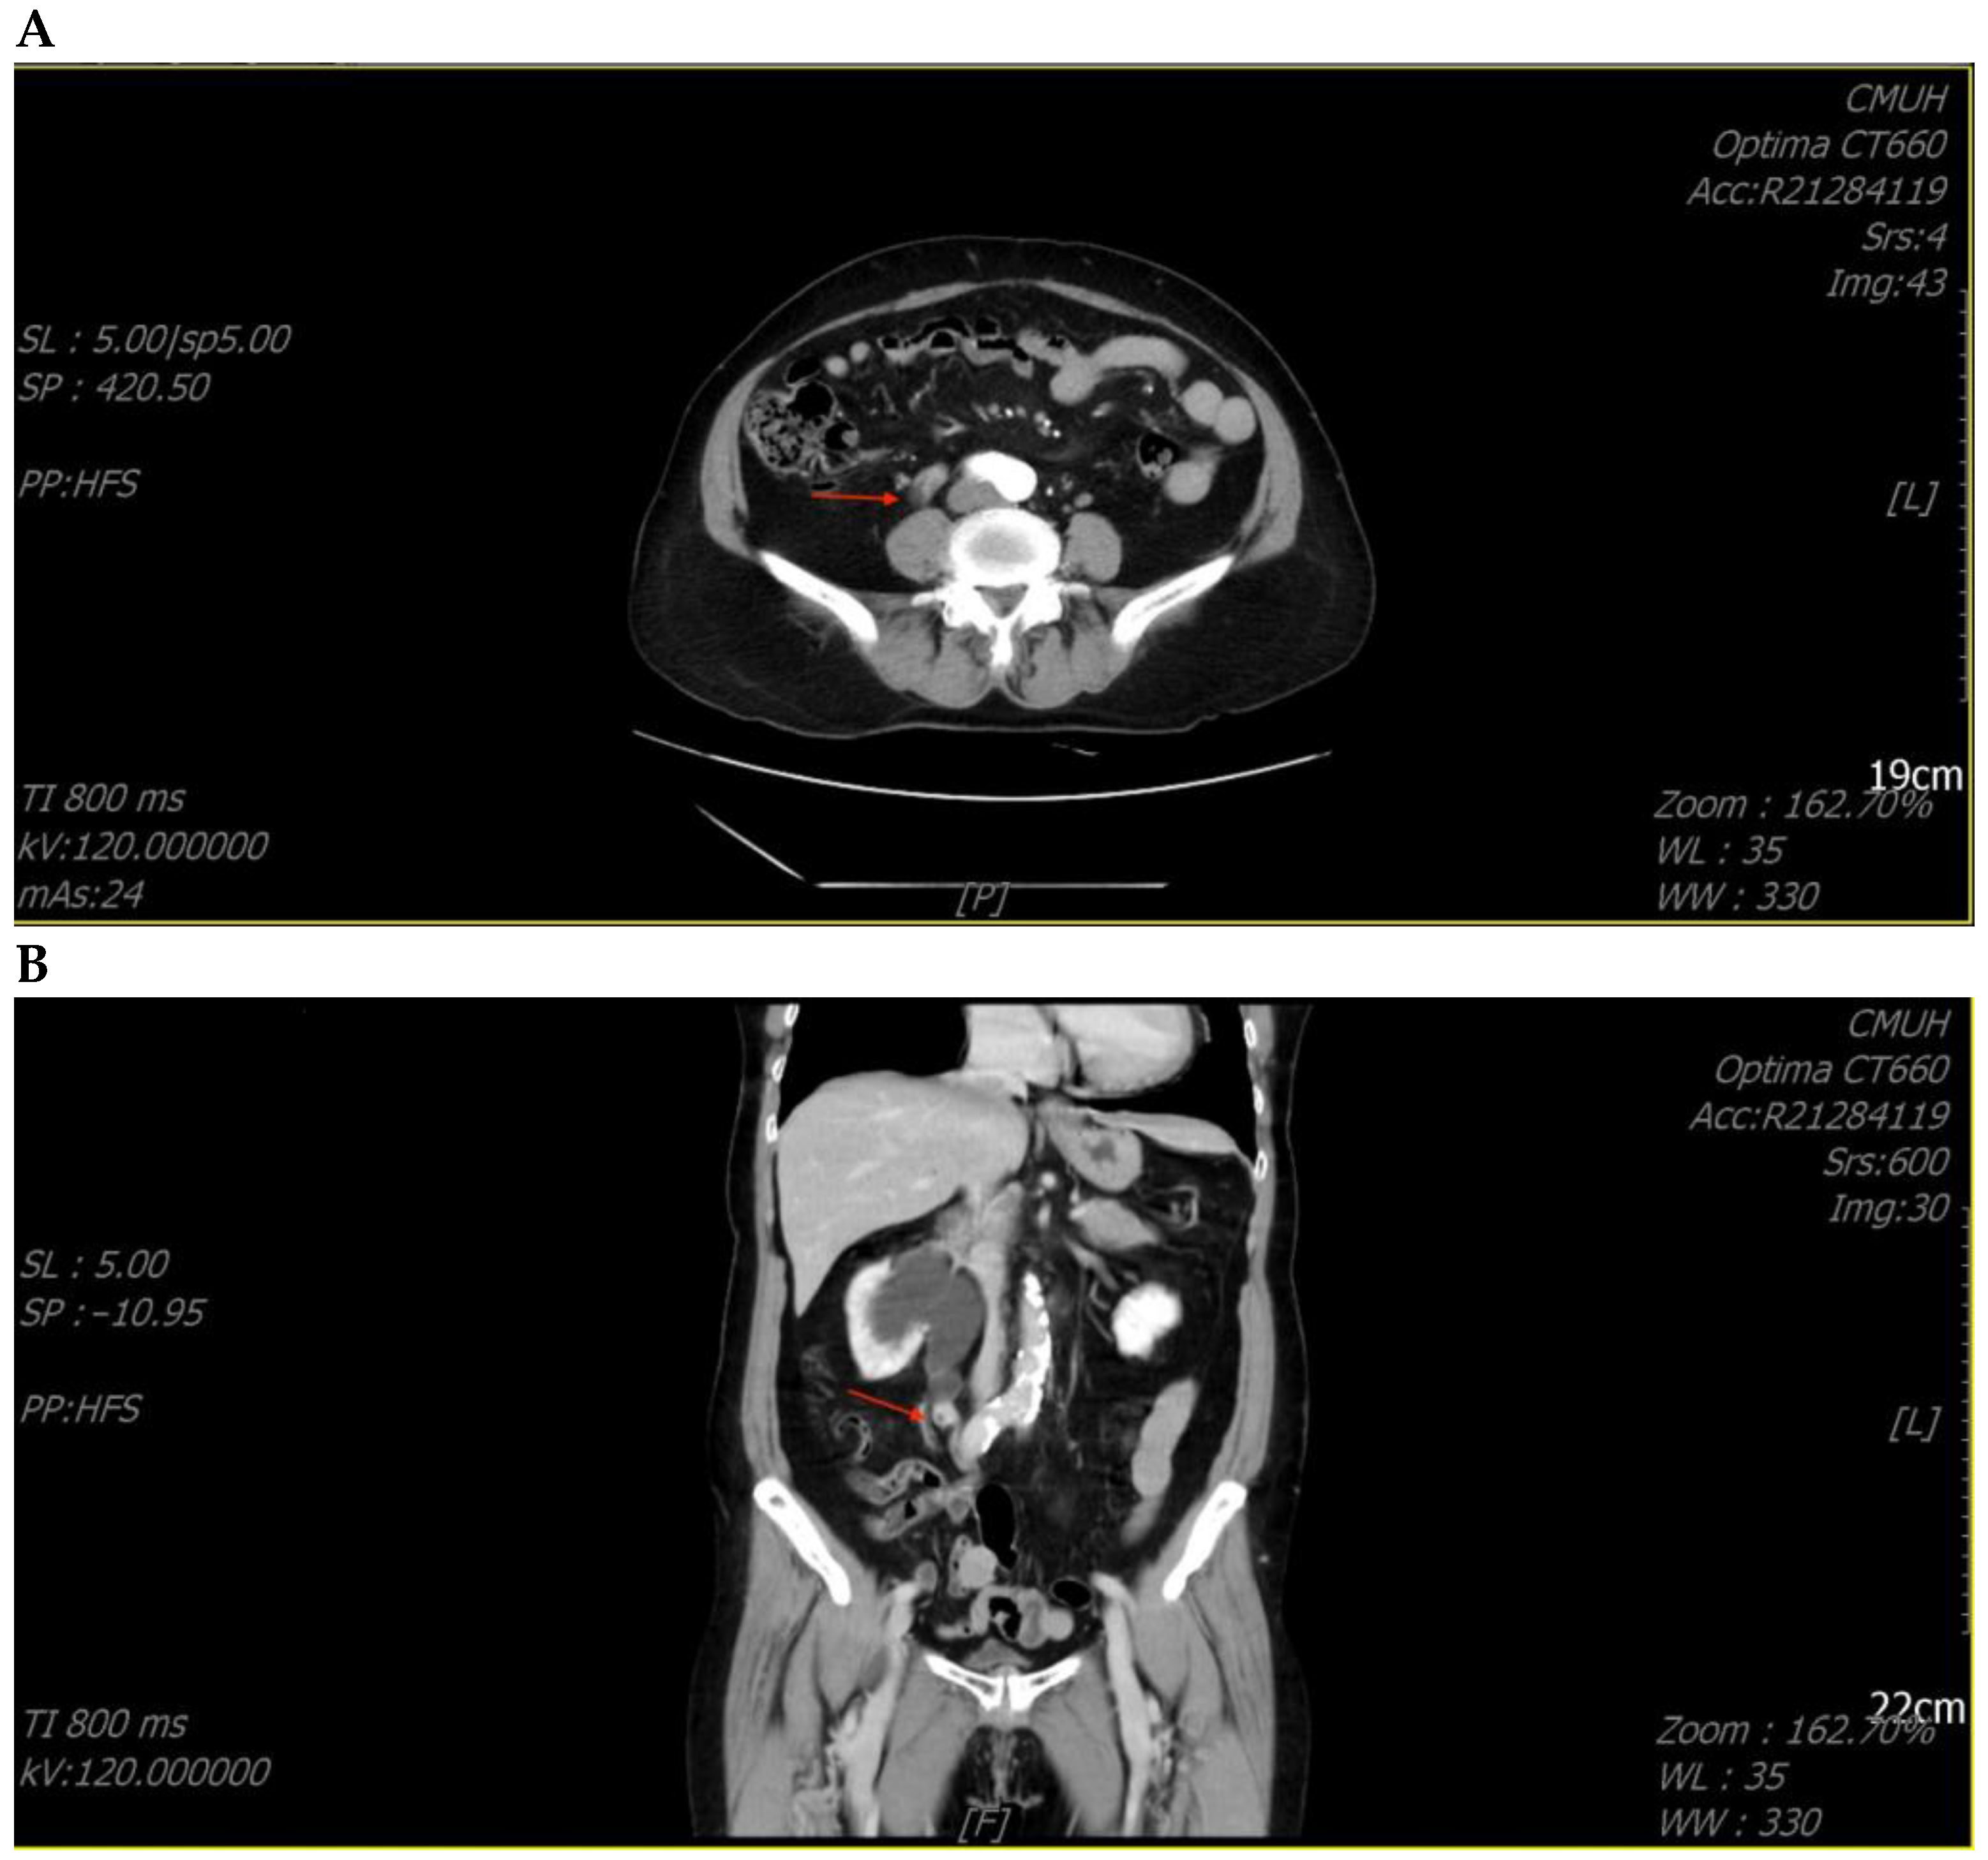

She underwent ureterorenoscopic surgery under the impression of a ureteral stone with obstruction. During the operation, a small stone was found with a tumor-like lesion below the stone. An endoscopic biopsy was performed during the operation, and the pathology report was chondrosarcoma. The tumor was heterologous and composed of epithelioid cell and chondrosarcoma components. The tumor’s immunoprofile was CK (+, only in the epithelioid tumor cells), vimentin (+, in both the epithelioid cells and chondrosarcoma cells), S100 (+, only in the chondrosarcoma cells), and GATA3 (−) (Figure 2). The picture was compatible with carcinosarcoma. Computed tomography (CT) of the abdomen revealed a tumor mass obstructing the upper ureter with proximal dilatation (Figure 3).

Figure 3. Computed tomography of the abdomen revealed a tumor (arrowhead) in the right upper ureter with proximal dilatation. (A) Coronary view; (B) Sagittal view.